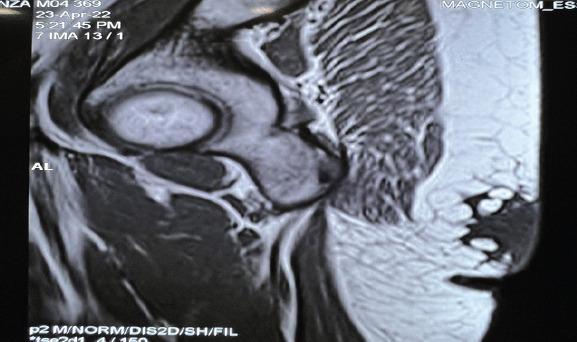

This article reports the case of a 43-year-old woman that came into the orthopedic outpatient department with a history of two masses, one on each buttock. The patient had a history of surgical excision of adiponecrotic mass from the right knee a year back. All the three masses appeared around the same time. Ultrasonography was done to surgically excise the left gluteal mass. The histopathology of the excised mass then confirmed subcutaneous fat necrosis.

本文报告了一名43岁女性的病例,该患者因双侧臀部各有一个肿块的病史前来骨科门诊就诊。患者一年前有过右膝脂肪坏死性肿块手术切除史。所有这三个肿块几乎同时出现。对左侧臀部肿块进行了超声检查以便手术切除。切除肿块的组织病理学检查随后证实为皮下脂肪坏死。